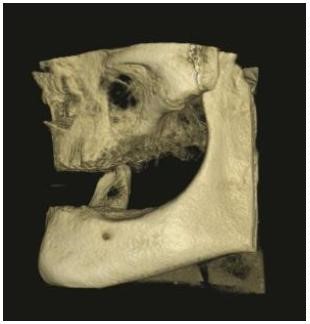

Para la planificación de la colocación de los implantes, la exploración clínica se complementa con la radiológica. La Radiografía Panorámica (OPG) (Figura 3) y la Tomografía Axial Computarizada (TAC) (Figura 4) nos permiten obtener la medición de los implantes y su punto de colocación.

Además, la Tomografía Computarizada de Haz Cónico (CBCT) nos informa sobre la cantidad y calidad ósea prequirúrgica. (Figura 5)